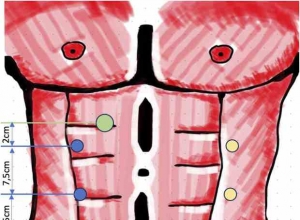

外科手套口在腹腔镜全胃切除术中的应用

一、技术的背景和原理外科手术手套端口技术主要用于单切口腹腔镜入口在执行阑尾切 ...